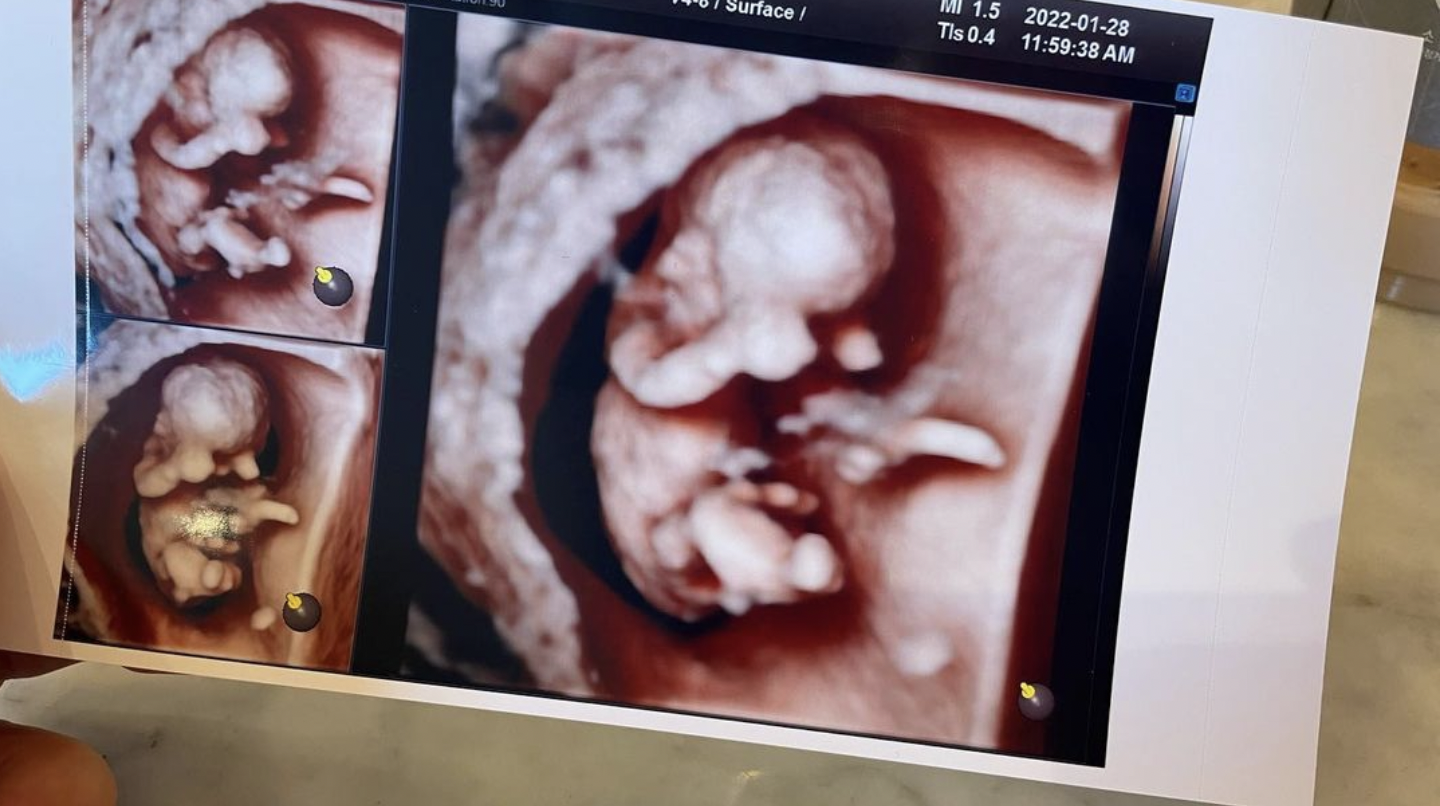

제이쓴은 자신의 인스타그램에 우리 아기 만나서 반가워, 이슨스 이제 아빠라면서 홍현희의 임신소식을 전했습니다. 이제 한 아이의 부모가 되는 둘의 소식에 동료 연예인들의 축하 물결이 이어졌습니다.